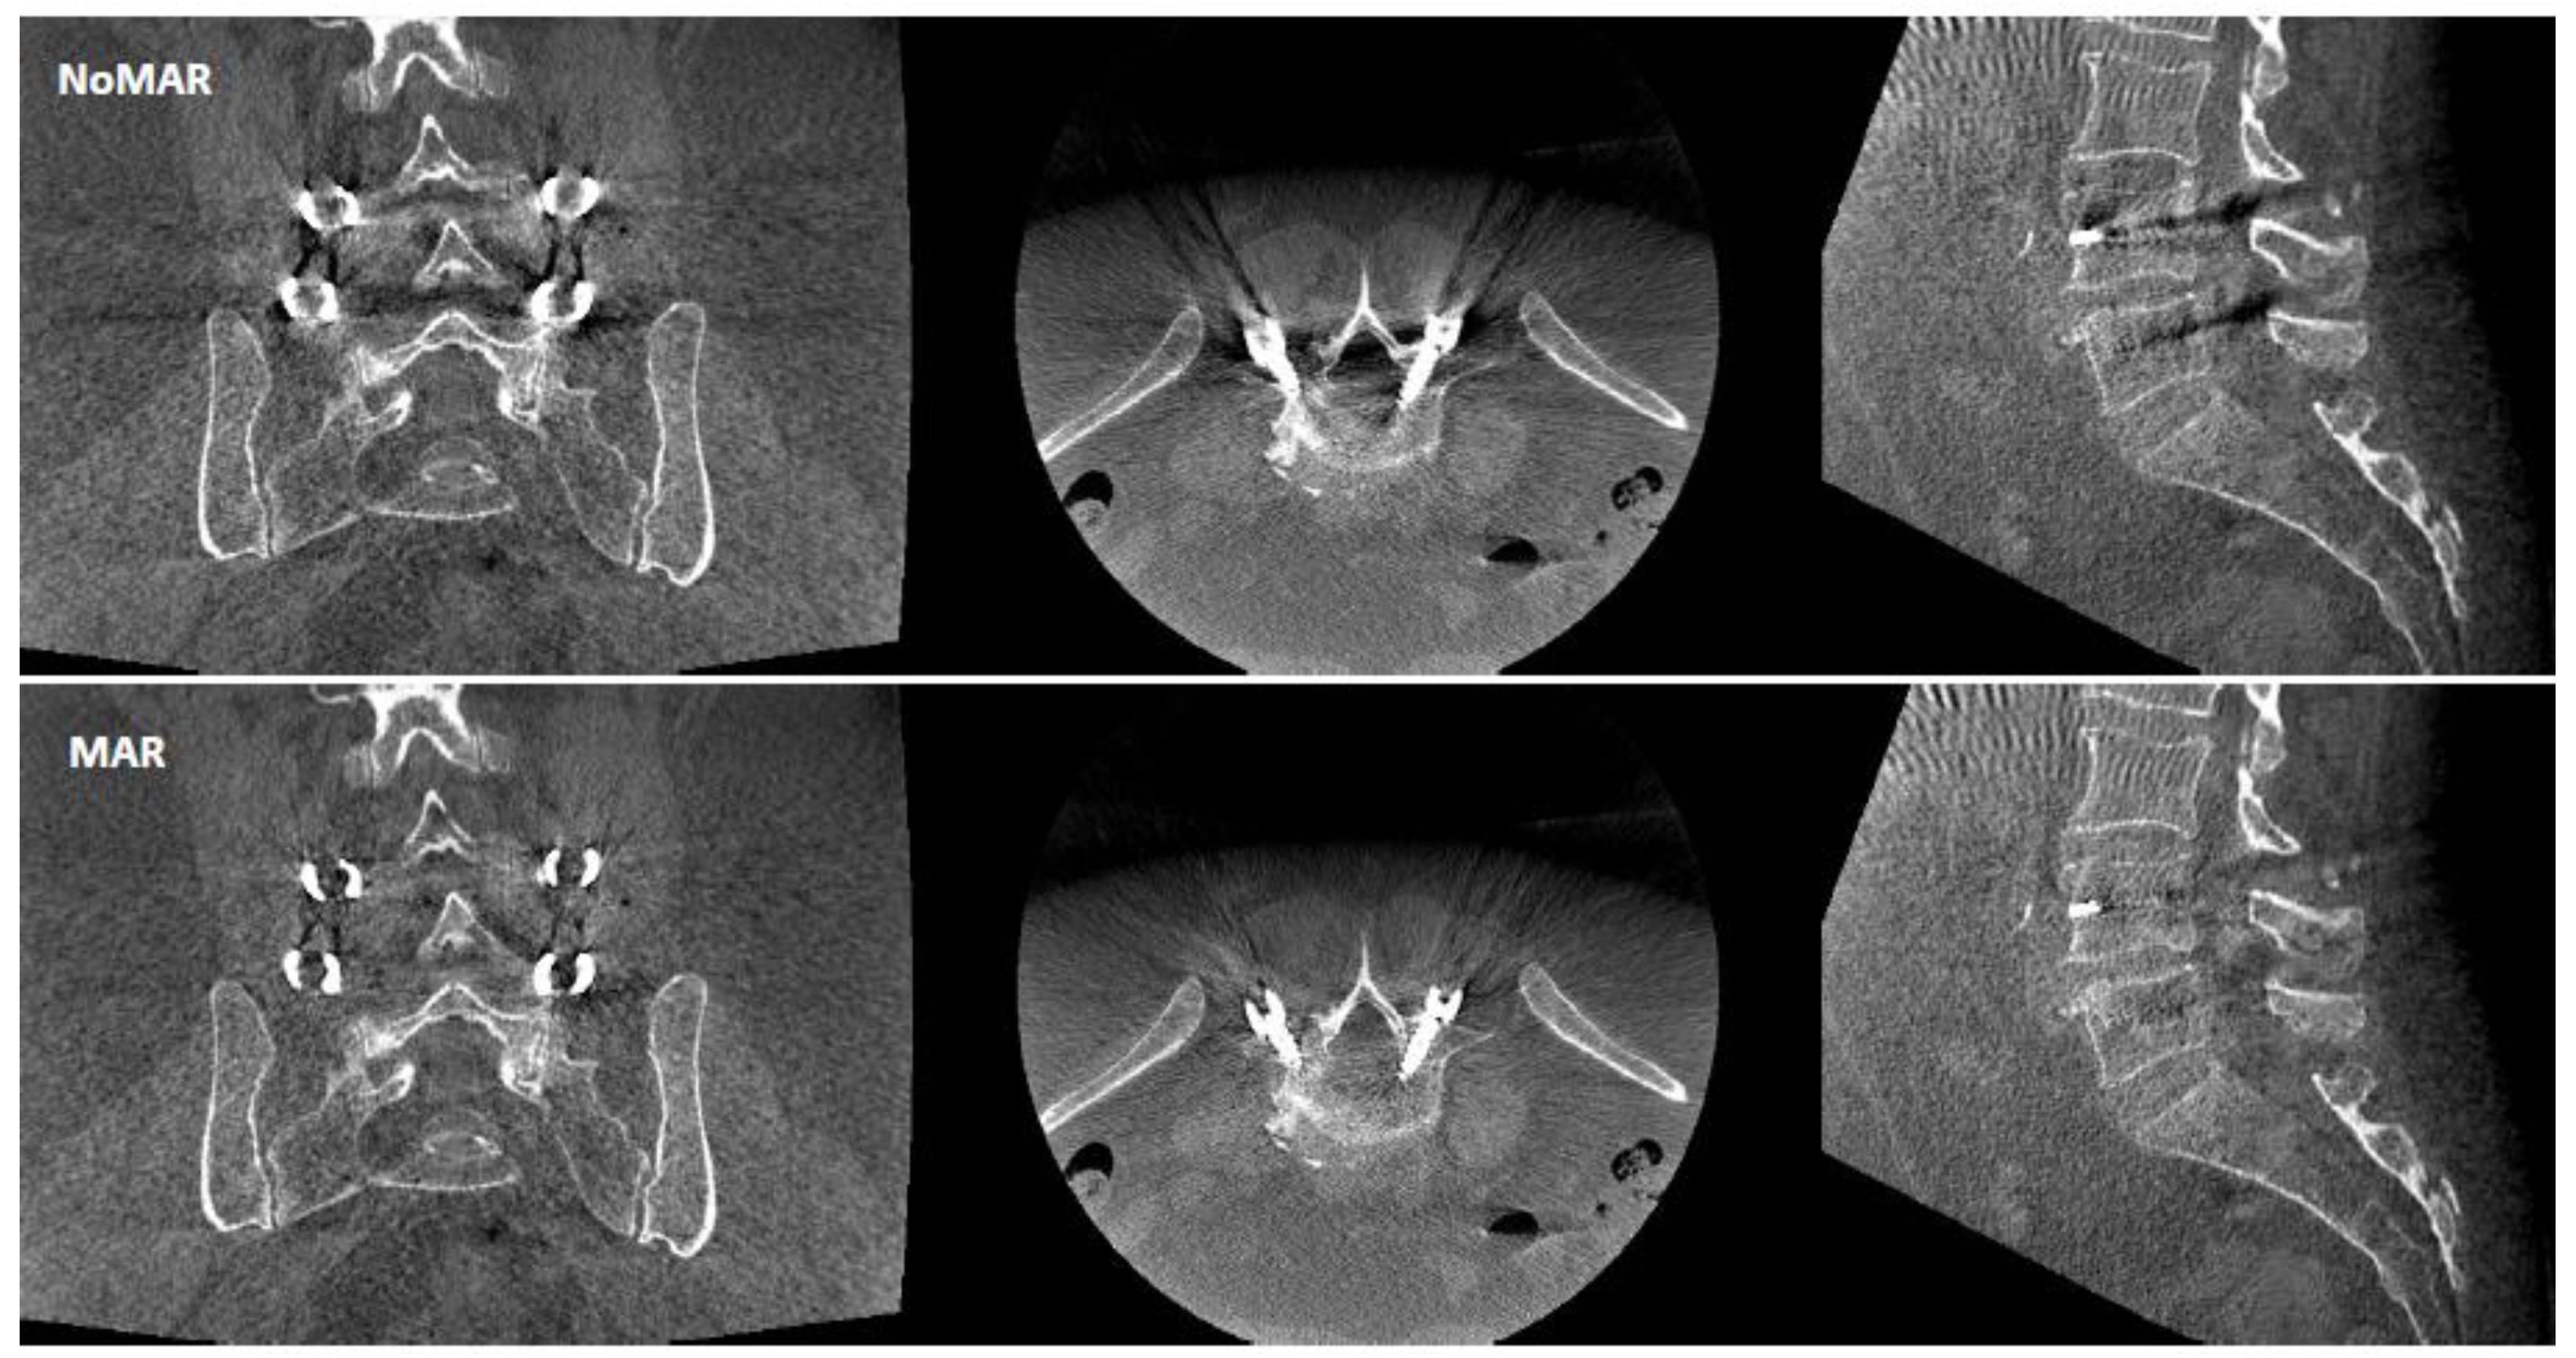

2.3. Image Analysis